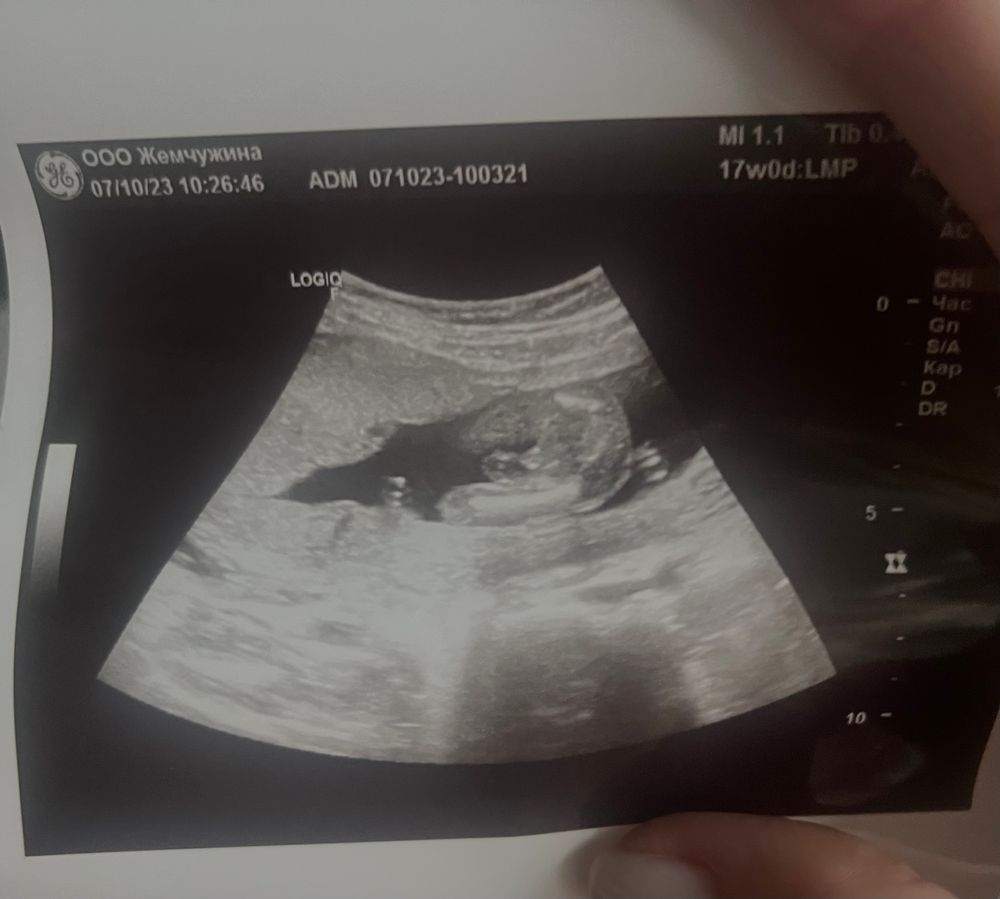

Илона в Клуб беременных 2 года 18 неделек, ну тут все понятно кого ждем))))) Пол малыша 😹Могу теперь закрашивать кружок Посмотрите еще 20 записей на эту тему Отменить Ответить Мама Света Поздравляю) пусть растет крепким и здоровым 🤗 07.10.2023 Ответить Счастье есть Прям песенка сразу в голове "он показывал п...н" 💖 07.10.2023 Ответить Екатерина Ух ты! Прям мощные, богатырские 💪 07.10.2023 Ответить Илона Екатерина, да🙈 07.10.2023 Ответить Даххха Мечтаю родить ДОЧКУ Поздравляю… 07.10.2023 Ответить Илона Даххха Мечтаю родить ДОЧКУ, 😹🙏🏻А вам желаю доченьку 07.10.2023 Ответить Даххха Мечтаю родить ДОЧКУ Lucky girl, спасибо. Может и соберусь… а пока только в мечтах. 07.10.2023 Ответить Пол ребёнка по 1 скринингу Опрос про пол на скрининге) Чаты Беременных Выберите чат: Январята-2026 Февралята-2026 Мартята-2026 Апрелята-2026 Майчата-2026 Июнята-2026 Июлята-2026 Августята-2026